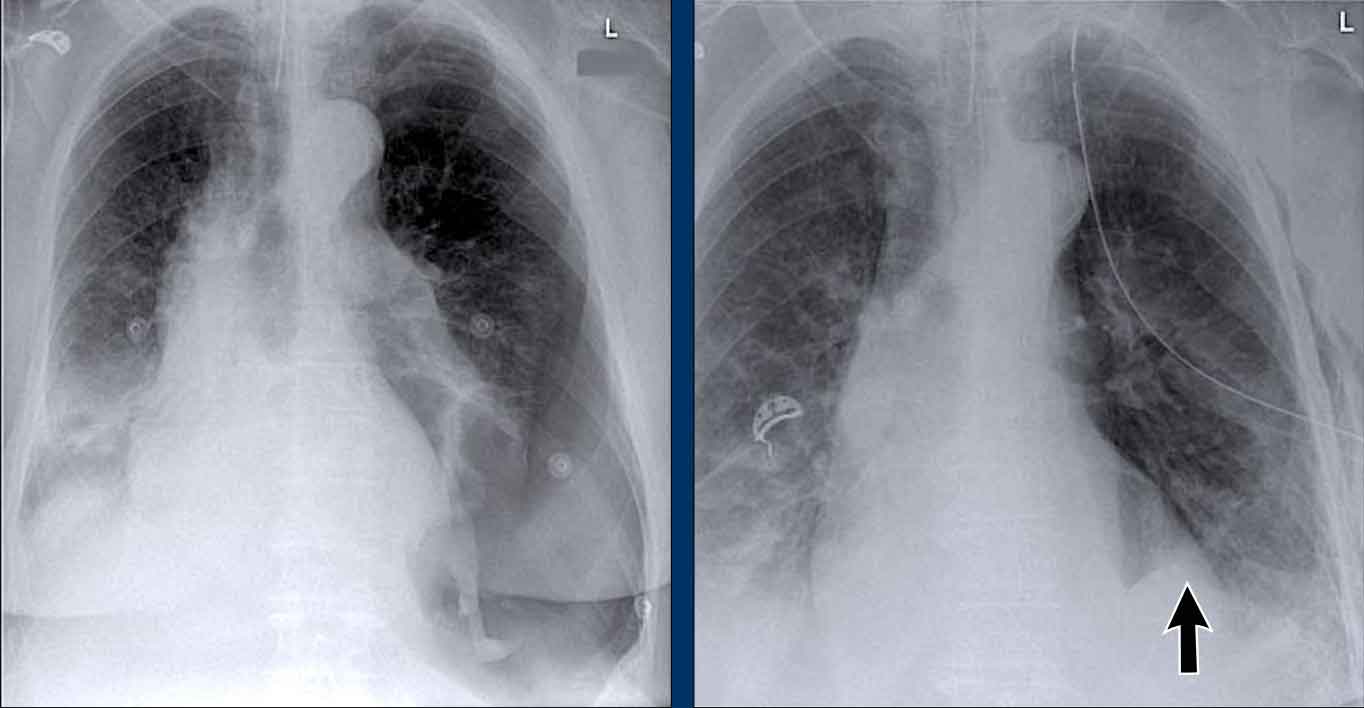

Clinical Case

A 70-year-old male patient presents following a fall down the stairs, complaining of severe right flank pain.

Imaging Findings

- On the PA chest radiograph, there is an absence of the right fifth digit.

- On the lateral view, there is increased density projected over the lower thoracic spine.

What is your diagnosis?

The findings are consistent with right lower lobe atelectasis.

On the PA view, note the abnormal contour of the right heart border. The right interlobar pulmonary artery is not visualized—this is because it is not surrounded by aerated lung, but rather by the collapsed right lower lobe, which lies adjacent to the right atrium.

On follow-up imaging, the right lower lobe has re-expanded, and the atelectasis has resolved.

This suggests that the atelectasis was likely due to post-traumatic hypoventilation with mucus plugging.

Also noted on the follow-up radiograph is the reappearance of the right fifth finger (black arrow), and restoration of a normal right heart border (white arrow), confirming re-expansion of the lower lobe.